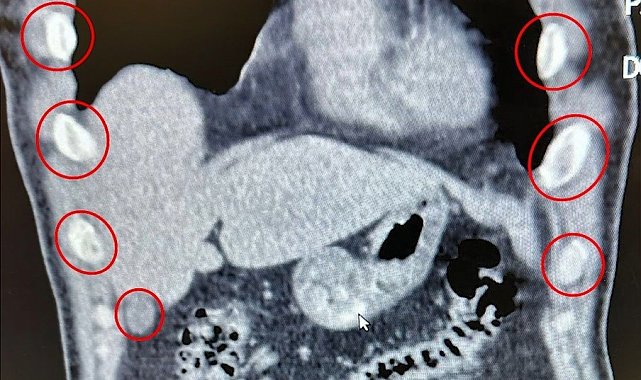

Midelerinden 136 kapsül uyuşturucu çıktı

Bitlis'te düzenlenen narkotik operasyonunda yabancı uyruklu iki şüpheli, midelerinde taşıdıkları 136 uyuşturucu kapsülleriyle yakalandı.

Bitlis İl Emniyet Müdürlüğü Narkotik Suçlarla Mücadele Şube Müdürlüğü ekipleri, uyuşturucu ile mücadele kapsamında önemli bir operasyona imza attı. Tatvan ilçesinde durdurulan bir otobüste yolcu olarak seyahat eden yabancı uyruklu 2 kişi gözaltına alındı. Şahısların yapılan tıbbi müdahalesinde, yuttukları 136 kapsül halinde toplam 1 kilo 48 gram metamfetamin ele geçirildi.